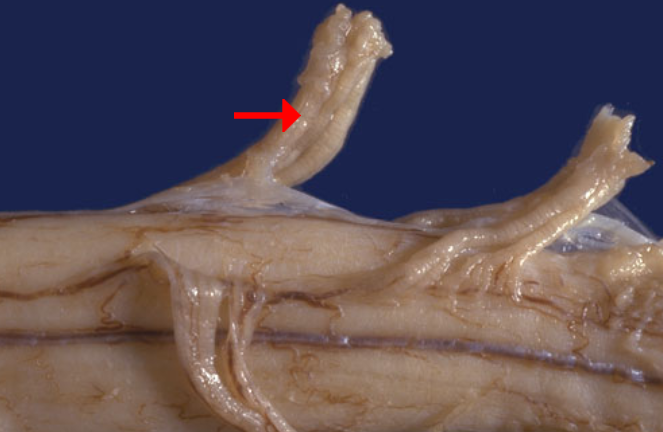

Label this region of the spinal cord

Dorsal sensory root

Label this region of the spinal cord

Ventral motor root